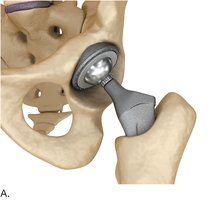

Hip Replacement

Total hip replacement involves removing the damaged femoral head and acetabulum and replacing them with prosthetic components.